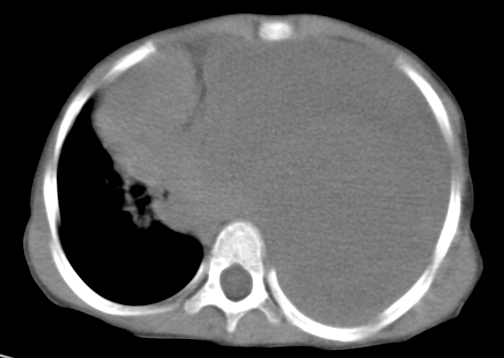

患儿 女 4岁,发热 咳嗽 胸透 考虑:左侧脓胸

左侧胸廓内见大量密实阴影,肺尖部尚有少量肺组织影,纵膈明显受压移位,肋骨未见明显受侵征象,虽然病人年龄较小,但如此大量的“积液”,还是要警惕,不同意一般感染,可结合穿刺脱落细胞学检查。

左侧大量胸腔积液。原因?

左侧张力性大量胸腔积液压迫性肺不张、感染;建议治疗后复查。

左侧大量胸腔积液,原因待查。